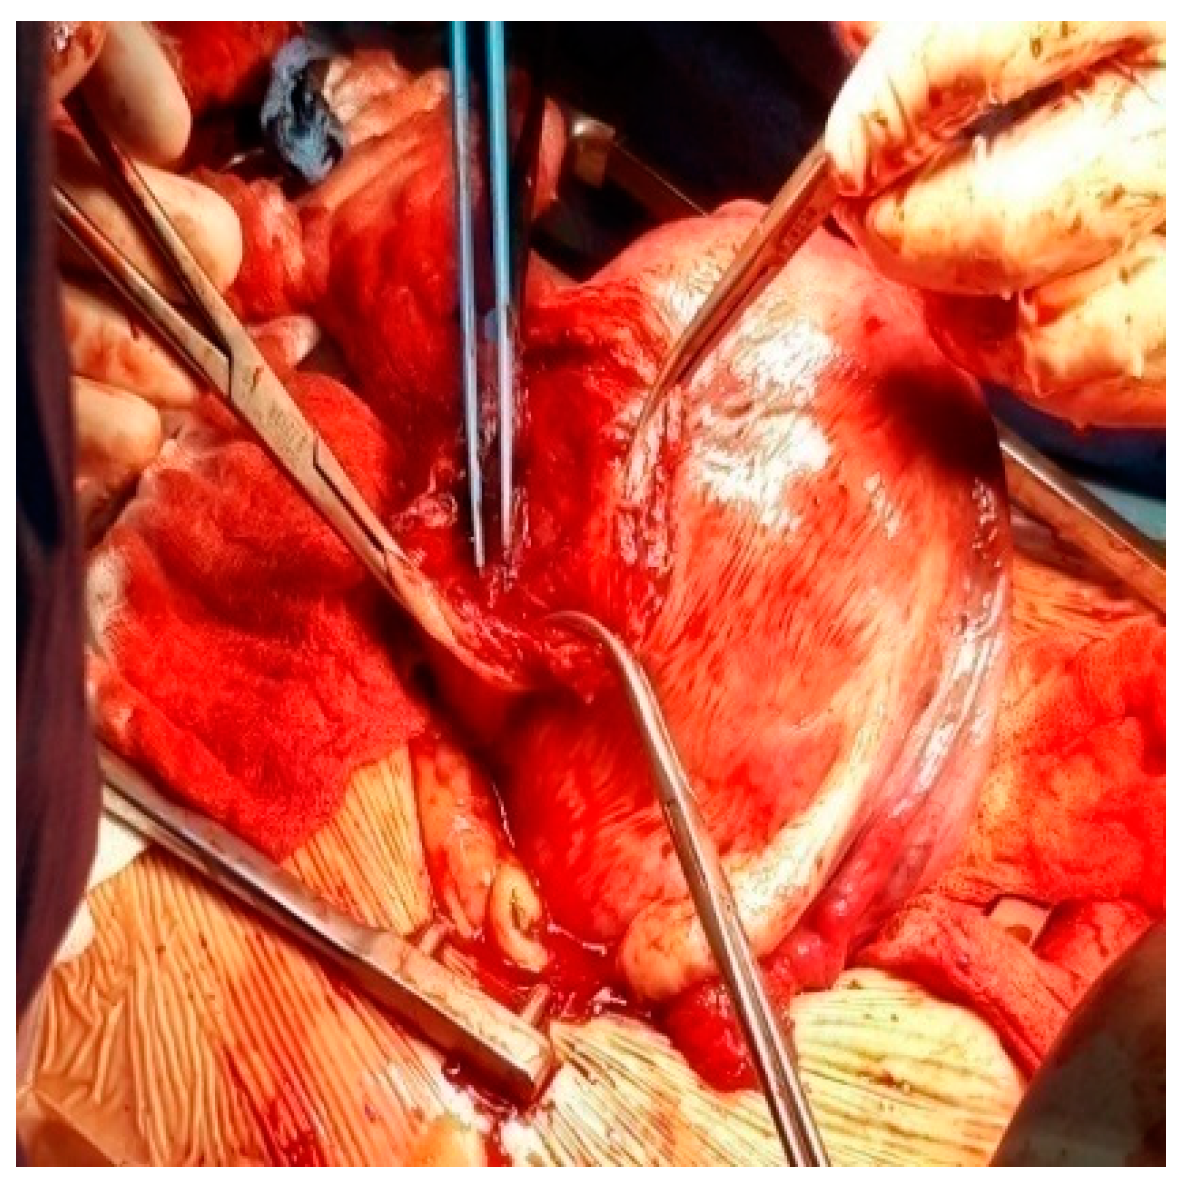

- Pergialiotis, V.; Sinanidis, I.; Louloudis, I.-E.; Vichos, T.; Perrea, D.N.; Doumouchtsis, S.K. Perioperative Complications of Cesarean Delivery Myomectomy: A Meta-Analysis. Obstet. Gynecol. 2017, 130, 1295–1303. [Google Scholar] [CrossRef]

- Goyal, M.; Dawood, A.S.; Elbohoty, S.B.; Abbas, A.M.; Singh, P.; Melana, N.; Singh, S. Cesarean Myomectomy in the Last Ten Years; A True Shift from Contraindication to Indication: A Systematic Review and Meta-Analysis. Eur. J. Obstet. Gynecol. Reprod. Biol. 2021, 256, 145–157. [Google Scholar] [CrossRef]

- Awoleke, J.O. Myomectomy during Caesarean Birth in Fibroid-Endemic, Low-Resource Settings. Obstet. Gynecol. Int. 2013, 2013, 520834. [Google Scholar] [CrossRef] [PubMed] [Green Version]